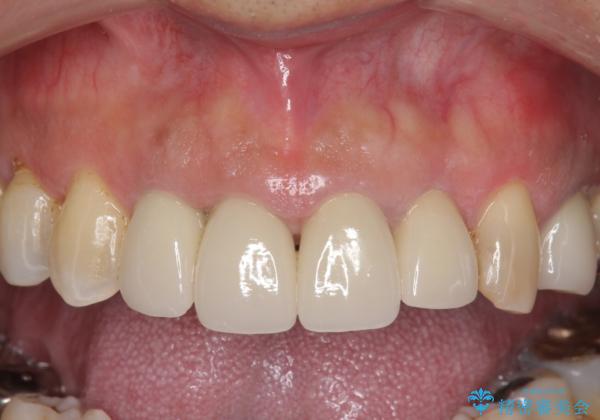

老朽化した前歯のクラウンやりかえ

- 10数年前に治療した上顎前歯のクラウンをやり替え、審美性を回復したいと希望され来院されました。

茶しぶの目立つ下顎前歯はPMTCを行うことで歯の自然な白さを回復しました。

- 48.4万円(税込)(仮歯・ジルコニアクラウン×4)費用は治療当時の料金となります